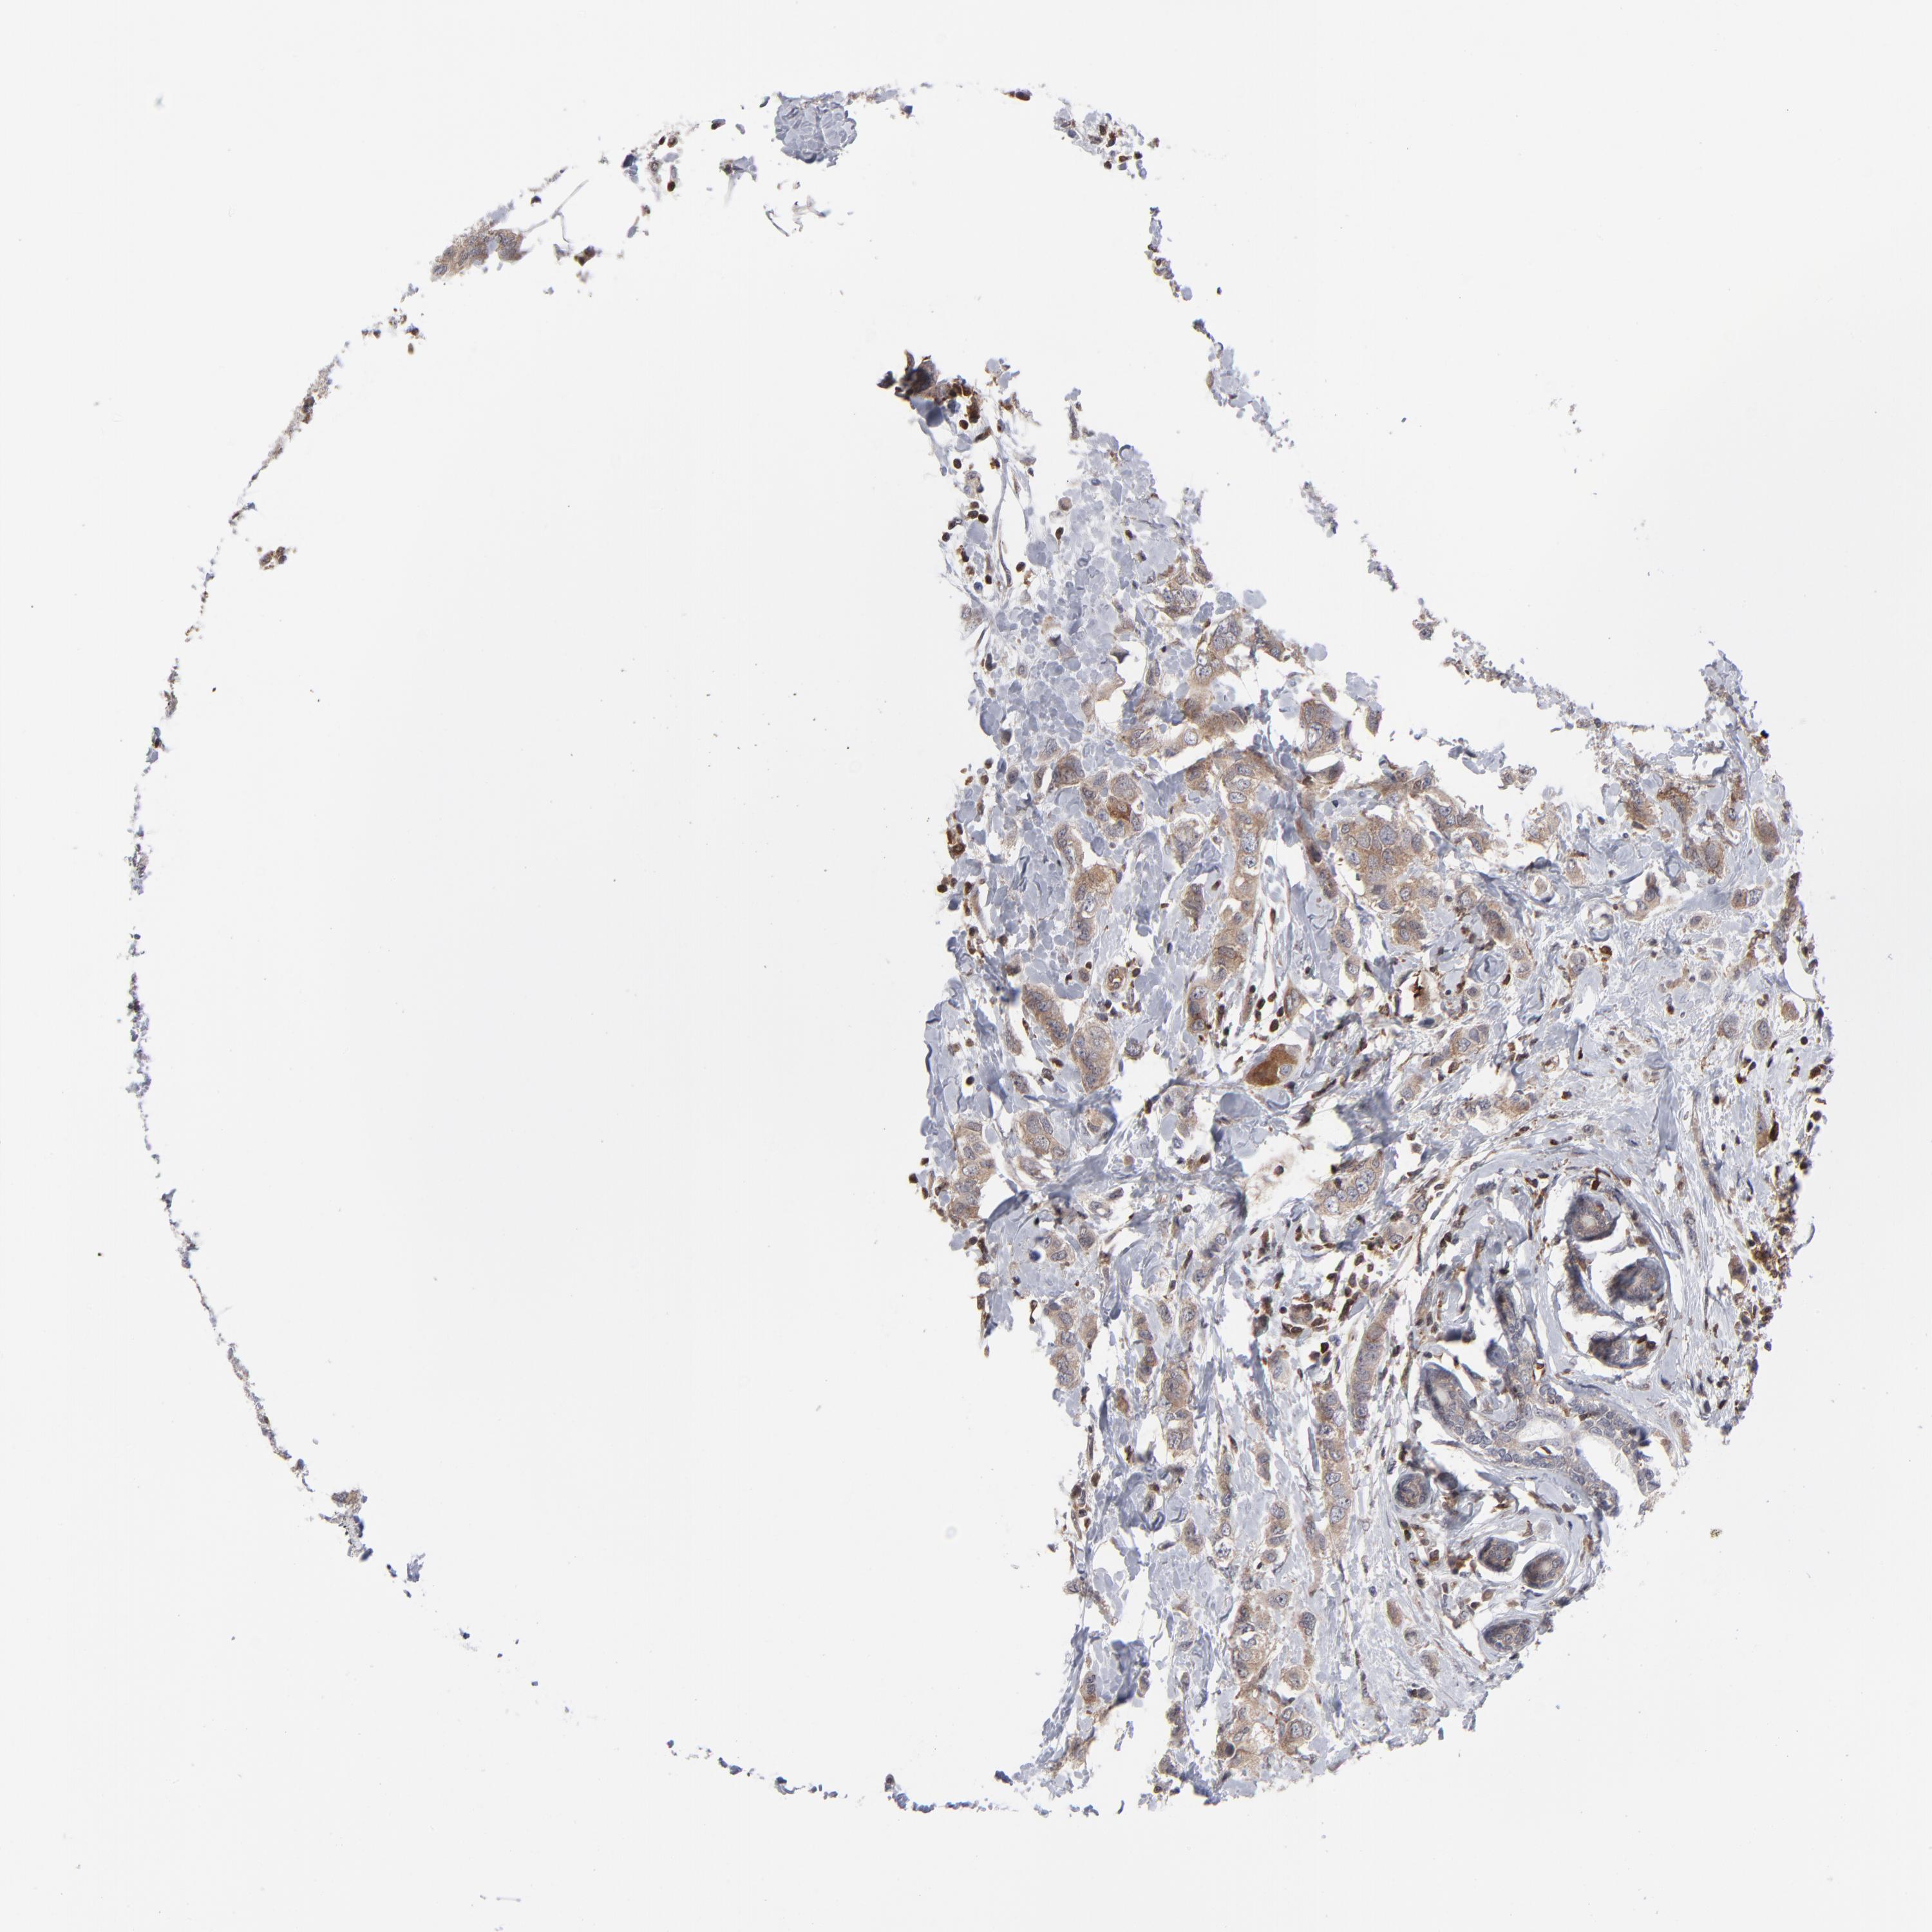

BRCA TCGA BRCA VALIDATION PROTEIN EXPRESSION